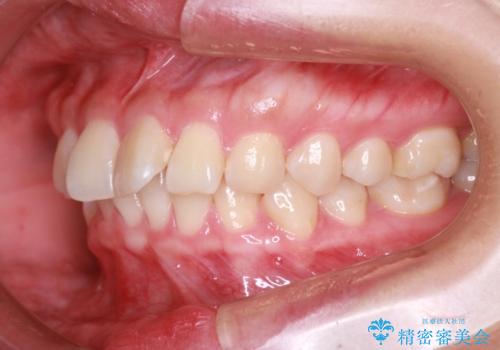

【インビザライン】翼状捻転+出っ歯を治したい

- 前歯の捻れと口元の突出を主訴に来院されました。

インビザラインを用いて上顎の遠心移動を行い、前歯を下げながら凸凹を綺麗に治すことができました。

歯を抜かない矯正治療を行う場合、口元は極端には変わりません。

今回は奥歯の遠心移動を行い、できる限り前歯を下げられるように治療を行いました。